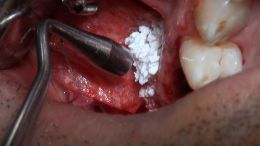

اصول مبانی GBR

+ اساتید گروه علمی بن تاژ پارس (زیرنظر پروفسور غلامی)

- جراحي توسط دکتر عميد از اساتید گروه علمی بن تاژ